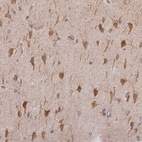

Immunohistochemical staining of human liver shows moderate cytoplasmic positivity in hepatocytes.